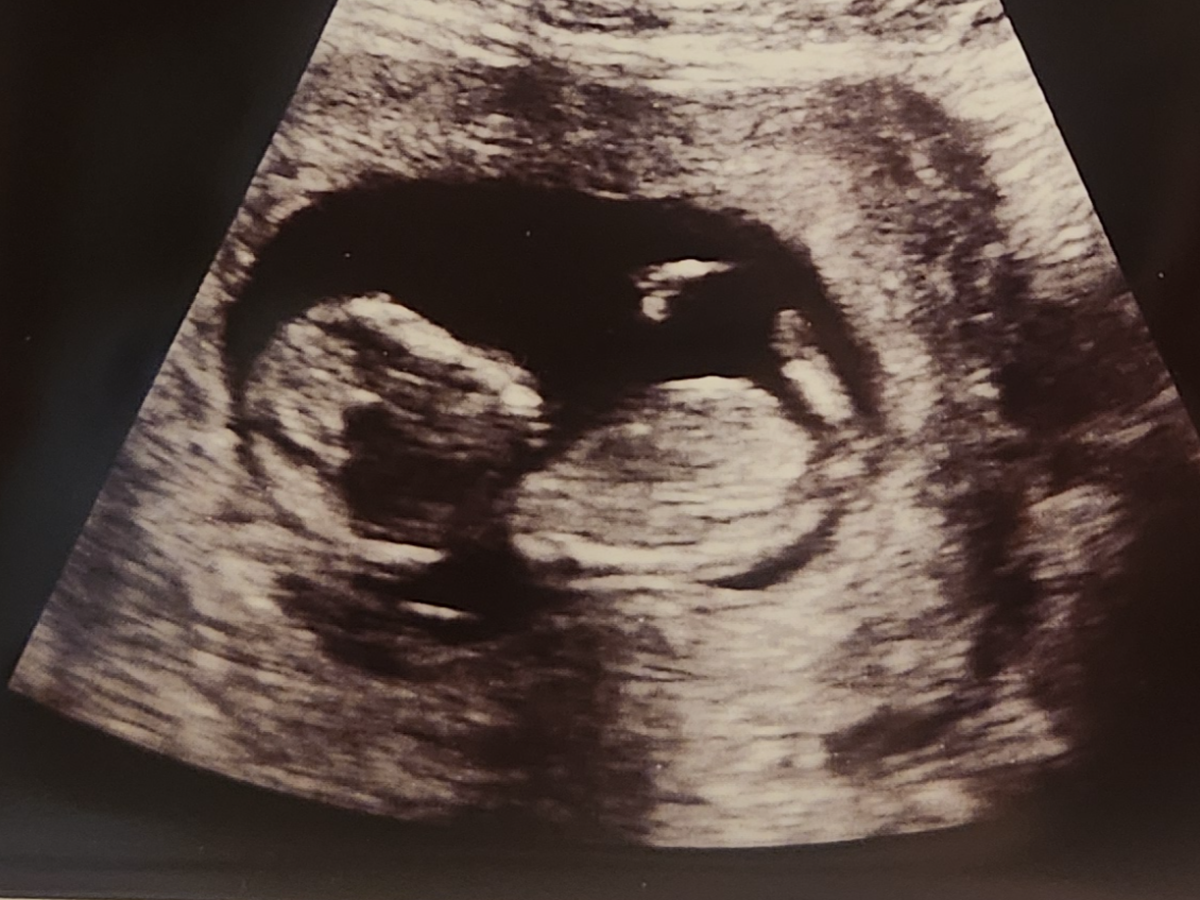

On Wednesday, I had a gut feeling something wasn’t right. I took the boys with me to the doctor, and I was right baby, Kaycen, no longer had a heartbeat. On Thursday, I was admitted to the hospital for surgery.